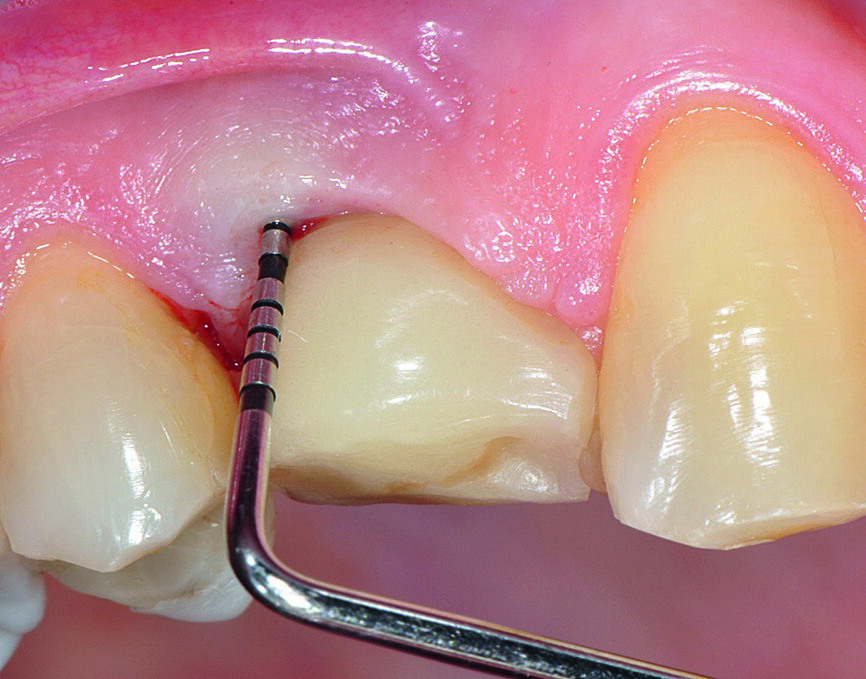

Figs. 1a : Implant en position 14 affecté par une péri-implantite : sondage péri-implantaire avec la couronne prothétique in situ

Fig b : Implant en position 14 affecté par une péri-implantite : sondage péri-implantaire après retrait de la couronne prothétique.